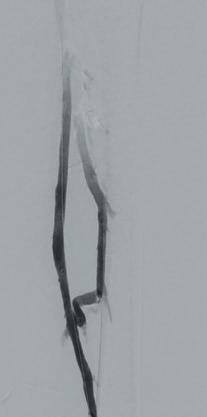

Arteriogram, left lower extremity

An arteriogram of the left lower extremity was performed via antegrade left common femoral artery access based on preoperative review of the lower extremity arteriogram from Uzbekistan. Scattered non-calcified plaque with moderate to high-grade stenoses were identified in the proximal and mid superficial femoral artery. Diffuse severe calcified tibial artery disease was identified. There was a long segment stenosis of the proximal and mid posterior tibial artery coupled with a more distal occlusion. The proximal peroneal artery was calcified and occluded with distal reconstitution identified. There was complete occlusion of the anterior tibial artery (Figure 2).